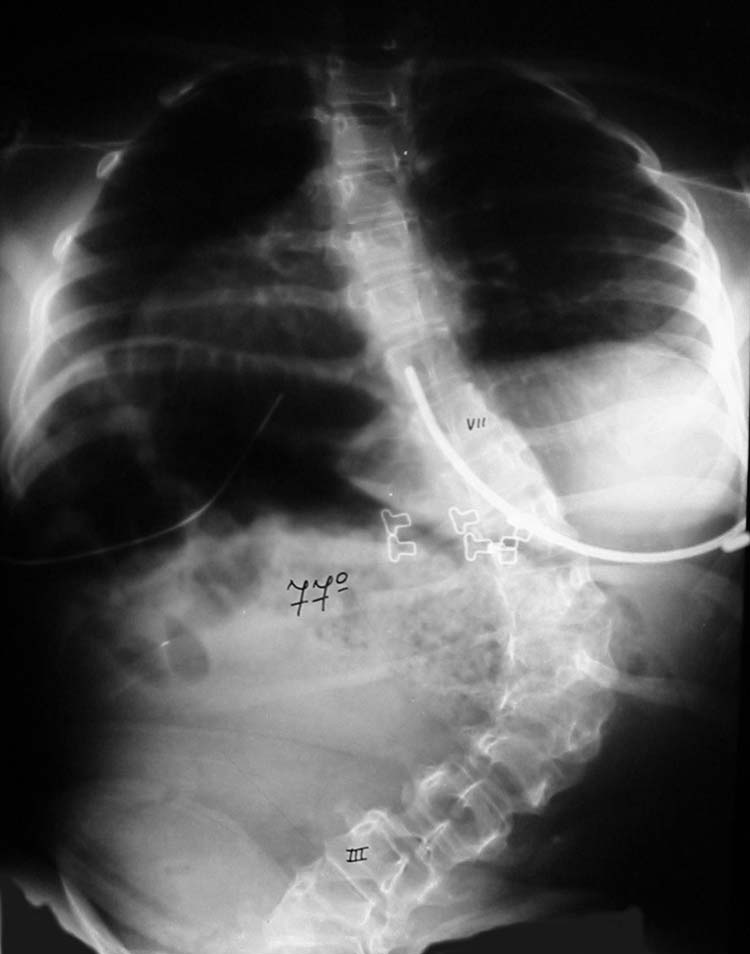

Columna, desviación 77º, antes operación Columna, desviación 34º, después operación